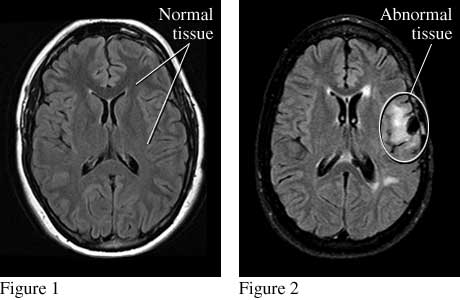

Top views of the brain show normal tissue (see figure 1) and abnormal tissue (from an injury) that causes seizures (see figure 2).